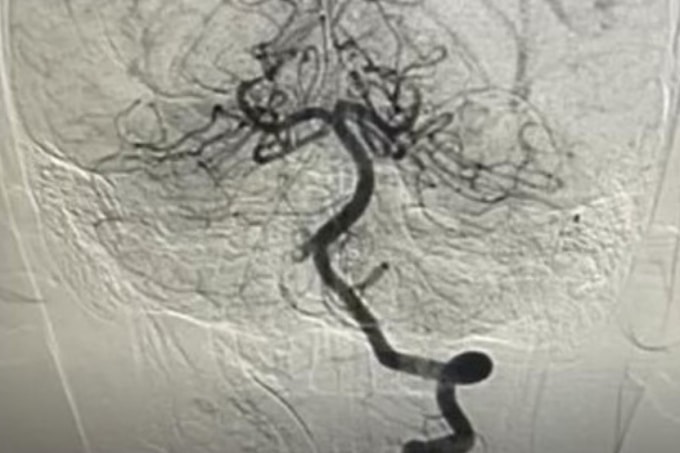

Ngày 8/2, BS.CK2 Nguyễn Minh Tiến, Phó giám đốc Bệnh viện Nhi đồng Thành phố, cho biết bệnh nhi nhập viện trong tình trạng nguy kịch. Kết quả MRI cho thấy bé bị nhồi máu não cấp, kèm huyết khối gần như tắc hoàn toàn động mạch đốt sống phải - tình trạng có thể gây tử vong hoặc để lại di chứng thần kinh nặng nề.

Các bác sĩ nhanh chóng hội chẩn liên khoa, chỉ định chụp mạch máu não và can thiệp nội mạch cấp cứu. BS.CK2 Trần Công Bảo Phụng và êkíp đã tiêu sợi huyết tại chỗ kết hợp hút huyết khối, tái thông hoàn toàn mạch máu não. Sau một tuần điều trị, bệnh nhi tỉnh táo, vận động phục hồi gần như bình thường, không ghi nhận di chứng thần kinh.